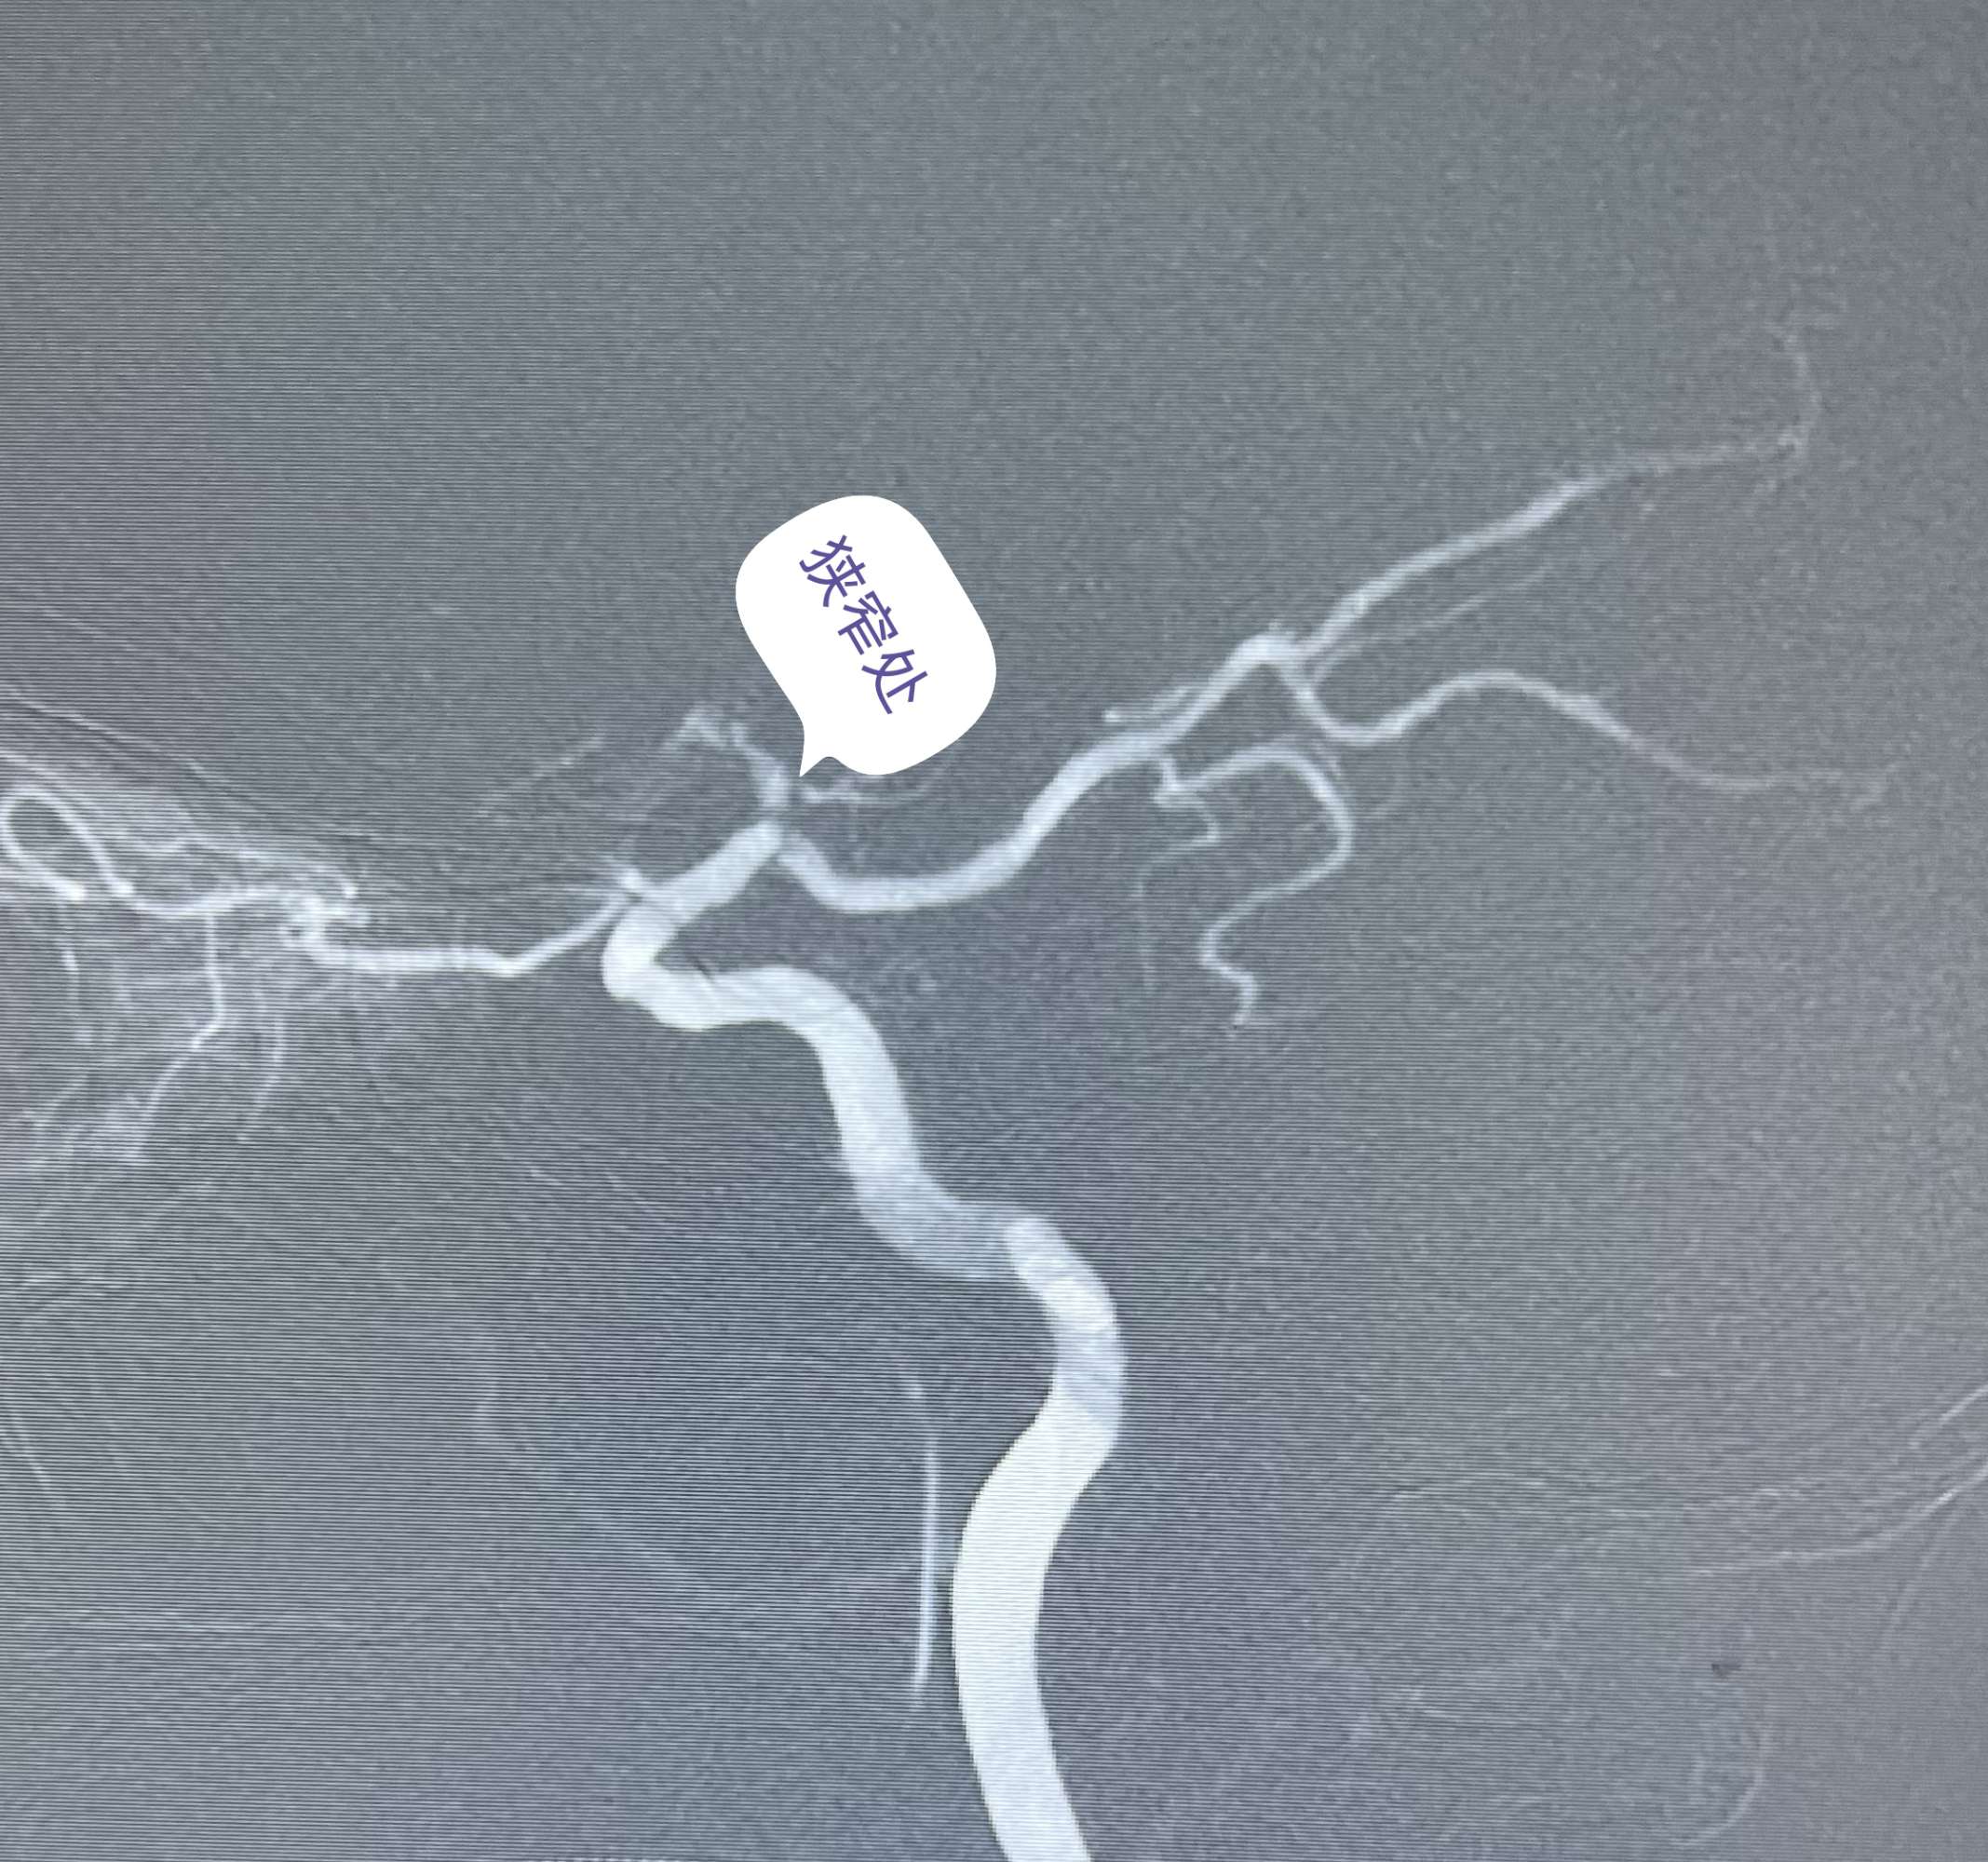

张某,男性,72岁,因“右侧肢体乏力不适三个月”入院。

CT及CTA提示左侧大脑灌注不足,左侧大脑中动脉M1狭窄。考虑此处串通支较多,予以搭桥手术。

术中游离颞浅动脉,暴露大脑中动脉M4段,行STA-MCA吻合术。

半年后患者来我科复查DSA。颞浅动脉与M4血管吻合满意,颈外动脉造影可见大脑中动脉显影,天堑造通途。。。